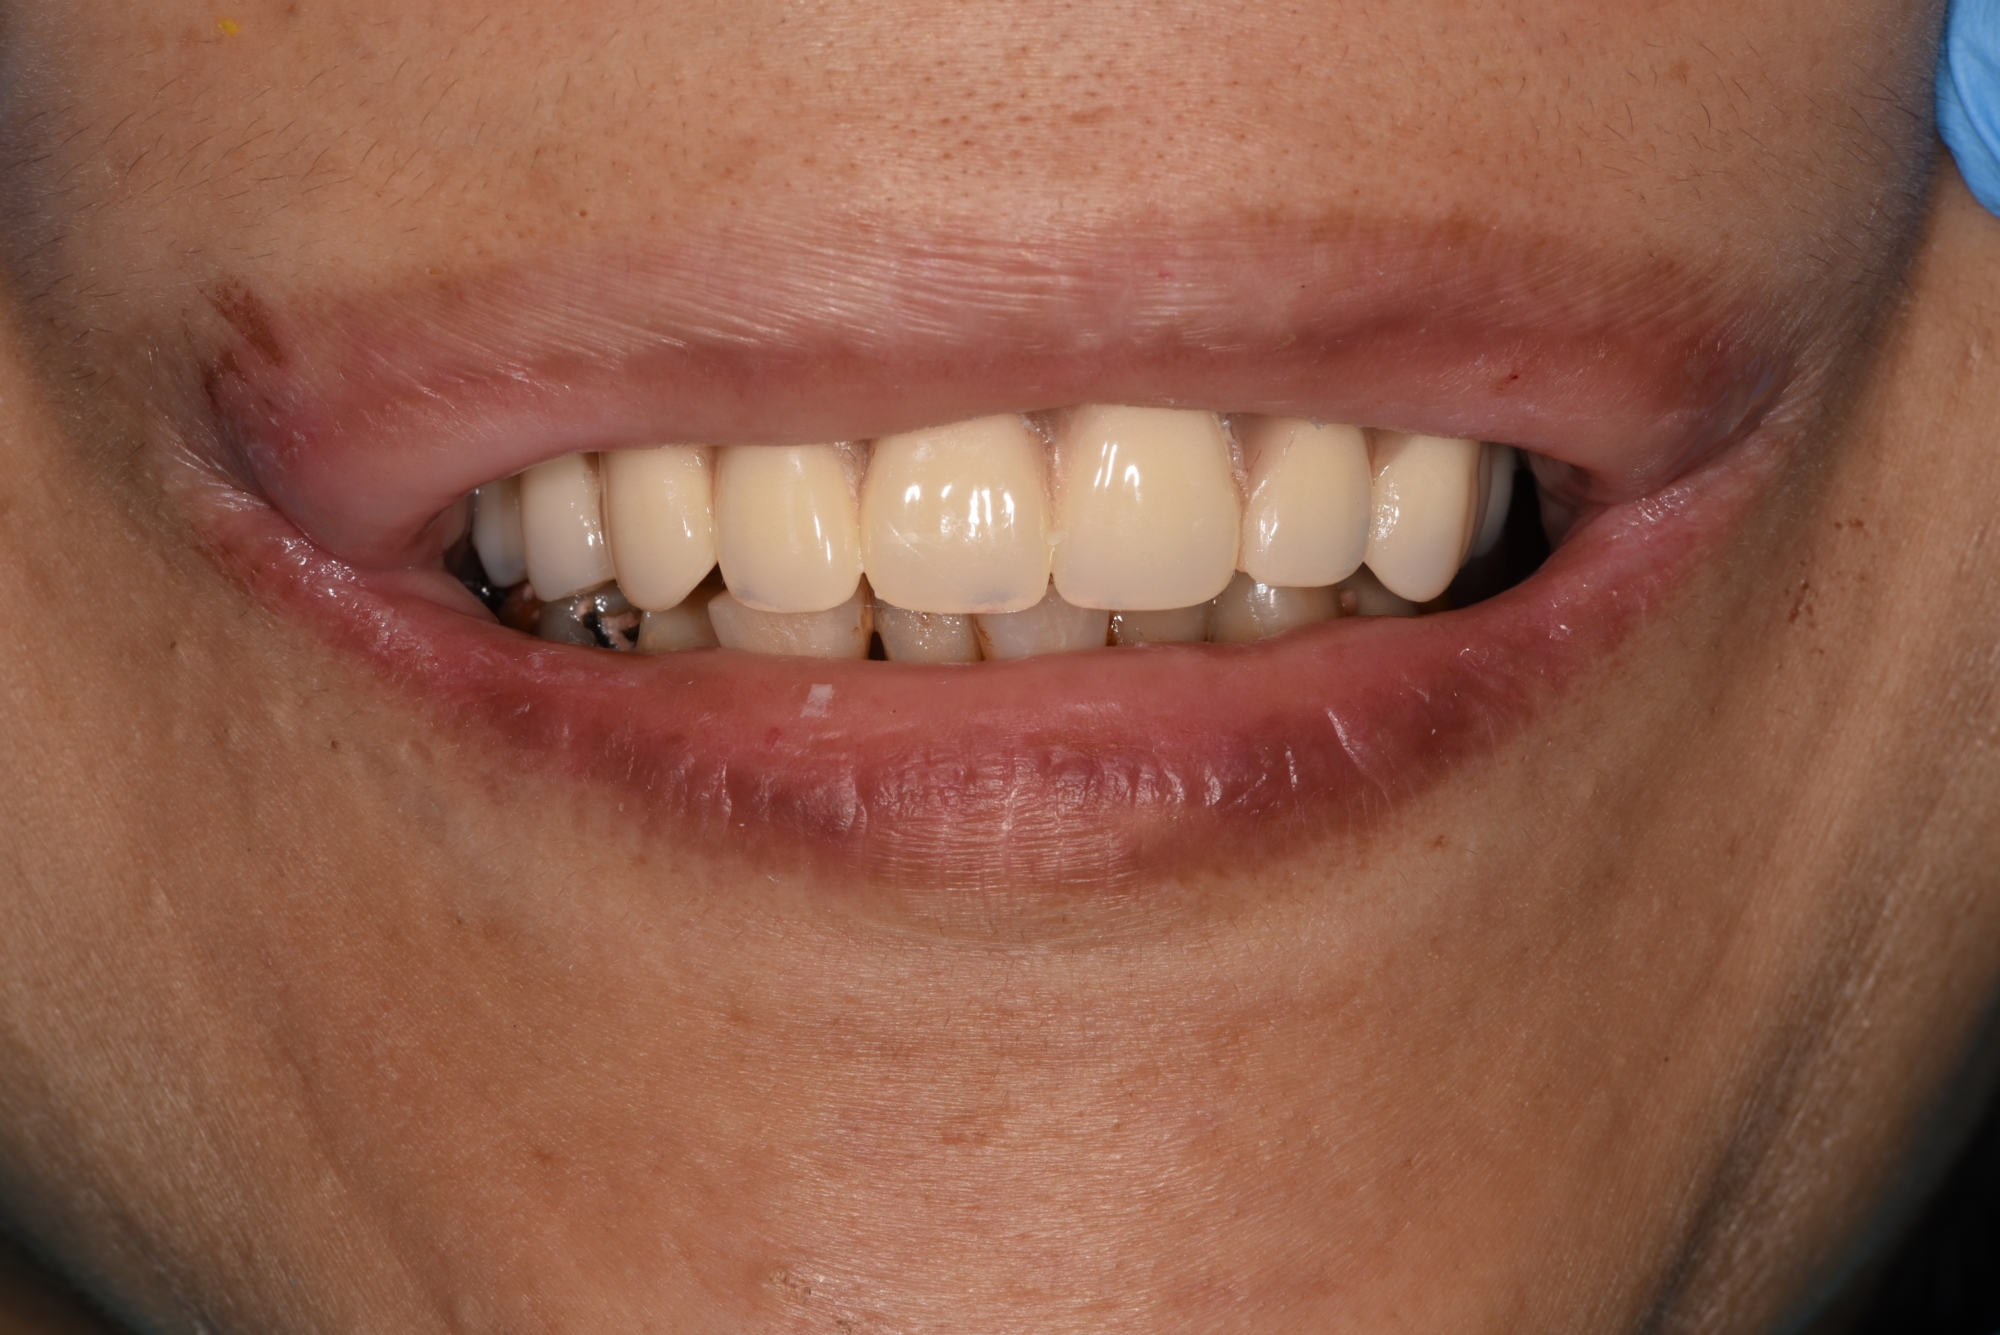

病友長期假牙有問題,某天突然掉落斷裂,經過一日全口重建固定式ALL On 4 假牙,同事朋友都沒發現她牙齒不見,只覺得隔天變得更美了